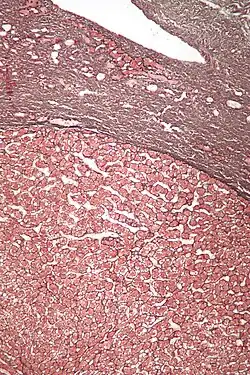

| Micrograph of a hepatic adenoma (bottom of image). H&E stain | |

Hepatic adenomas are, typically, well-circumscribed nodules that consist of sheets of hepatocytes with a bubbly vacuolated cytoplasm. The hepatocytes are on a regular reticulin scaffold and less or equal to three cell thick.

The histologic diagnosis of hepatic adenomas can be aided by reticulin staining. In hepatic adenomas, the reticulin scaffold is preserved and hepatocytes do not form layers of four or more hepatocytes, as is seen in hepatocellular carcinoma.

Cells resemble normal hepatocytes and are traversed by blood vessels but lack portal tracts or central veins.

Micrograph of hepatic adenoma. H&E stain

Micrograph of hepatic adenoma. H&E stain -